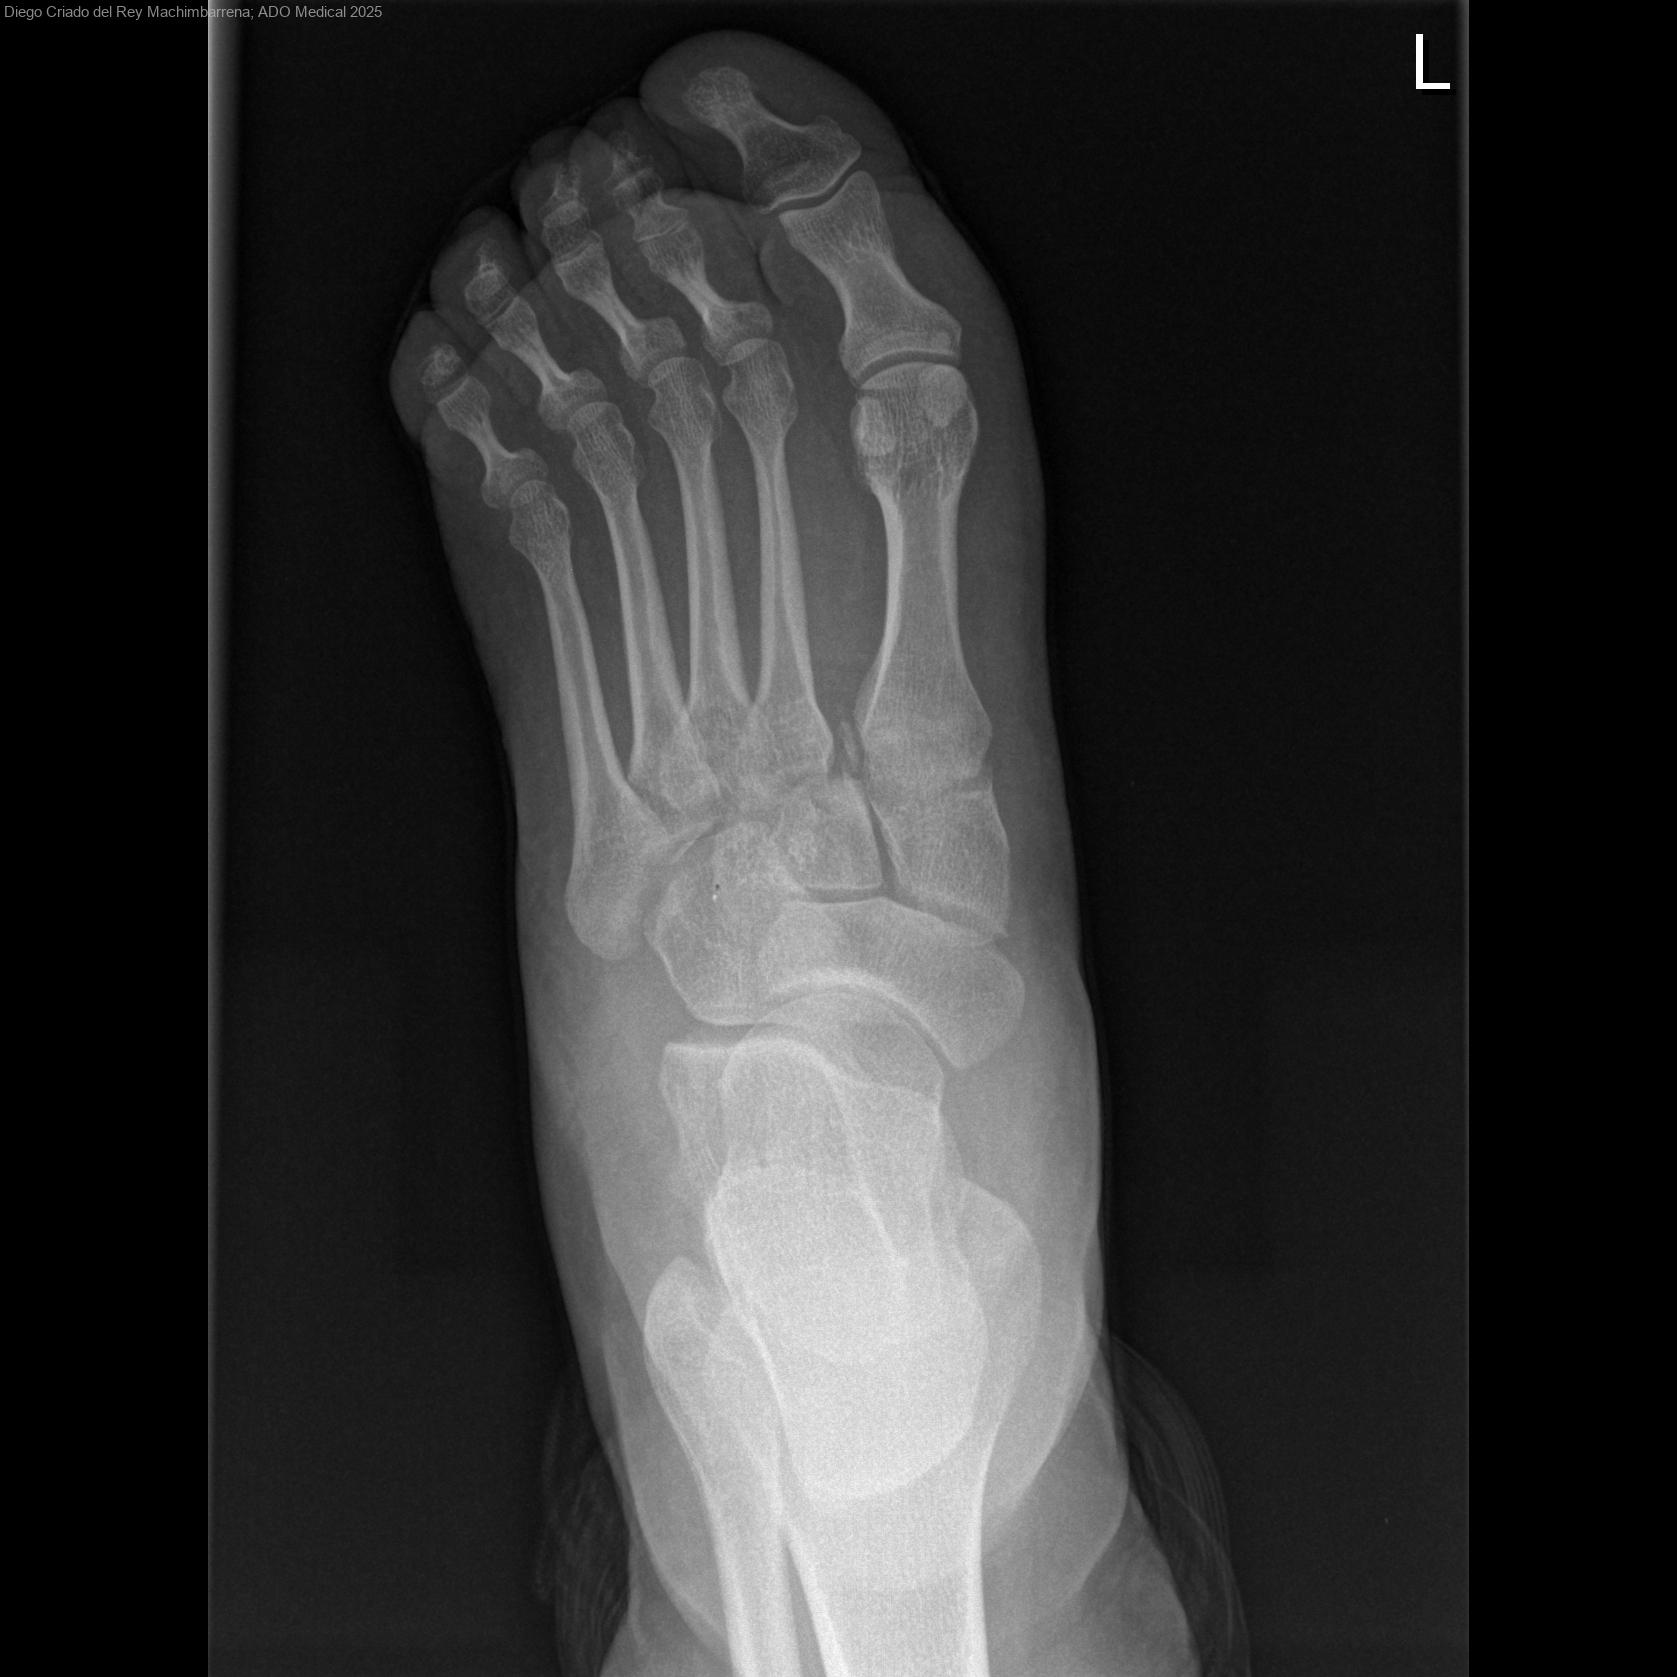

Fractura-Luxación de Lisfranc Crónica: Perspectivas Quirúrgicas y Conservadoras

La fractura-luxación de Lisfranc es una lesión del mediopié, a nivel de las articulaciones tarsometatarsianas, que cuando no se diagnostica en fase aguda puede evolucionar hacia una forma crónica. Estas situaciones suelen asociarse a dolor...